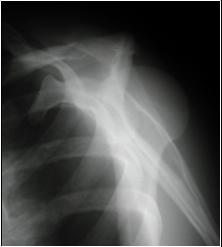

Y View in Posterior Dislocation

Y view